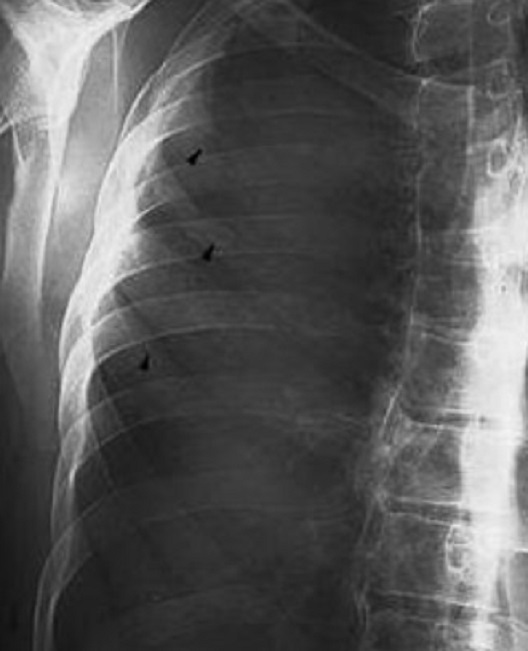

Aspect radiologique de

osteolyse de arch posterieue des côtes C5,6,7

droites ( flèche noire ) du osteite d'une SAPHO

syndrome . Plain film pulmonaire OAD |